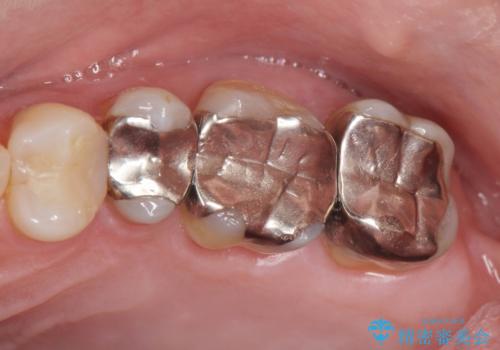

- 長年気になっていた銀歯を全て除去したい、とメタルフリー治療を希望され来院されました。

銀歯を丁寧に除去すると、銀歯の下で虫歯の再発やセメントの劣化が確認されたので、拡大鏡・マイクロスコープを用いて虫歯のみを丁寧に取り除いたのち、精密なセラミッククラウンの製作を進めます。